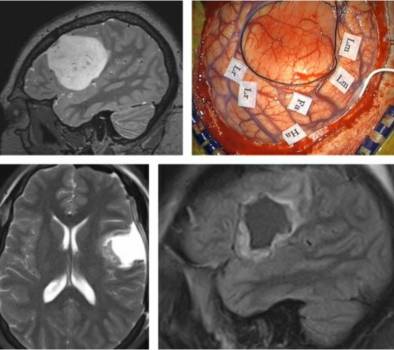

术前影像学检查可根据结构结构预测Broca区与Wernicke区是否被肿瘤累及以及是否有唤醒手术的指征。fMRI可以辅助判断。深部肿瘤可能需要对覆盖其上的皮层进行功能定位来规划合适的手术路径。

图3. 这个位于额叶后下方深部的肿瘤需要患者清醒状态下进行语言区定位,从而规划出可以安全到达肿瘤的手术路径(上图)。该高级别胶质瘤患者术后若出现功能缺陷会限制其生存获益。左侧开颅后,运动性语言中枢的最下方被标记为Lex(中图),在语言功能区前方切开皮层后显露肿瘤,最终安全的全切肿瘤(下图)。